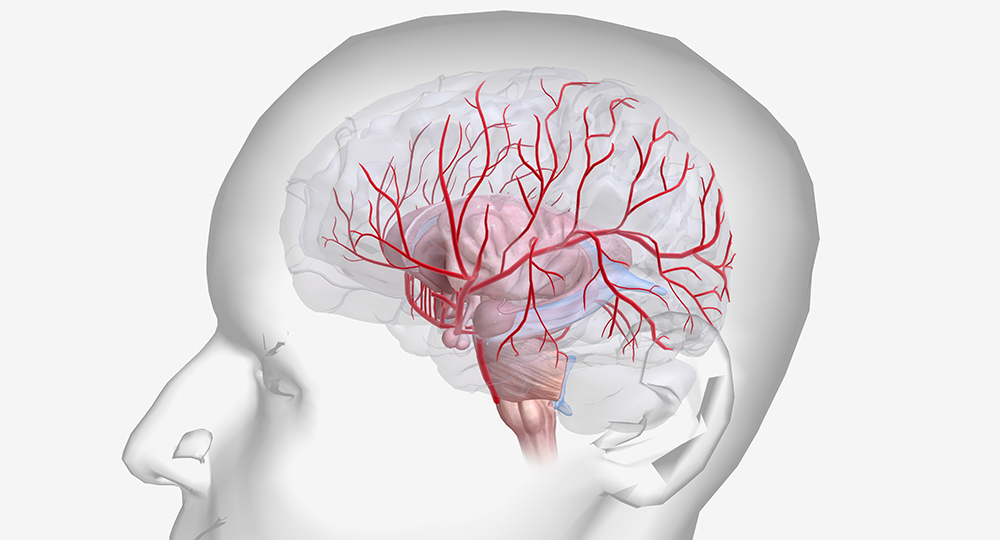

뇌졸중은 흔히 "중풍"으로 알려져 있으며, 갑작스러운 뇌혈관의 문제로 인해 발생하는 심각한 질환입니다. 이는 생명에 위협을 줄 수 있을 뿐만 아니라, 골든타임을 놓친다면 영구적인 장애를 남길 수도 있습니다. 뇌졸중의 주요 유형으로는 뇌경색과 뇌출혈이 있습니다. 뇌경색은 혈관이 막히는 현상을 말하며, 뇌출혈은 혈관이 터져 뇌조직으로 혈액이 유출되는 상태를 의미합니다.

뇌졸중은 뇌로 가는 혈류가 차단되거나 혈관이 터져 뇌세포가 손상되는 상태를 말합니다. 이 질환은 빠른 치료가 필수적인 응급 상황으로 분류됩니다. 뇌졸중의 원인은 혈전, 동맥경화, 고혈압 등이 있으며, 유전적 요인과 생활습관 또한 영향을 미칩니다.